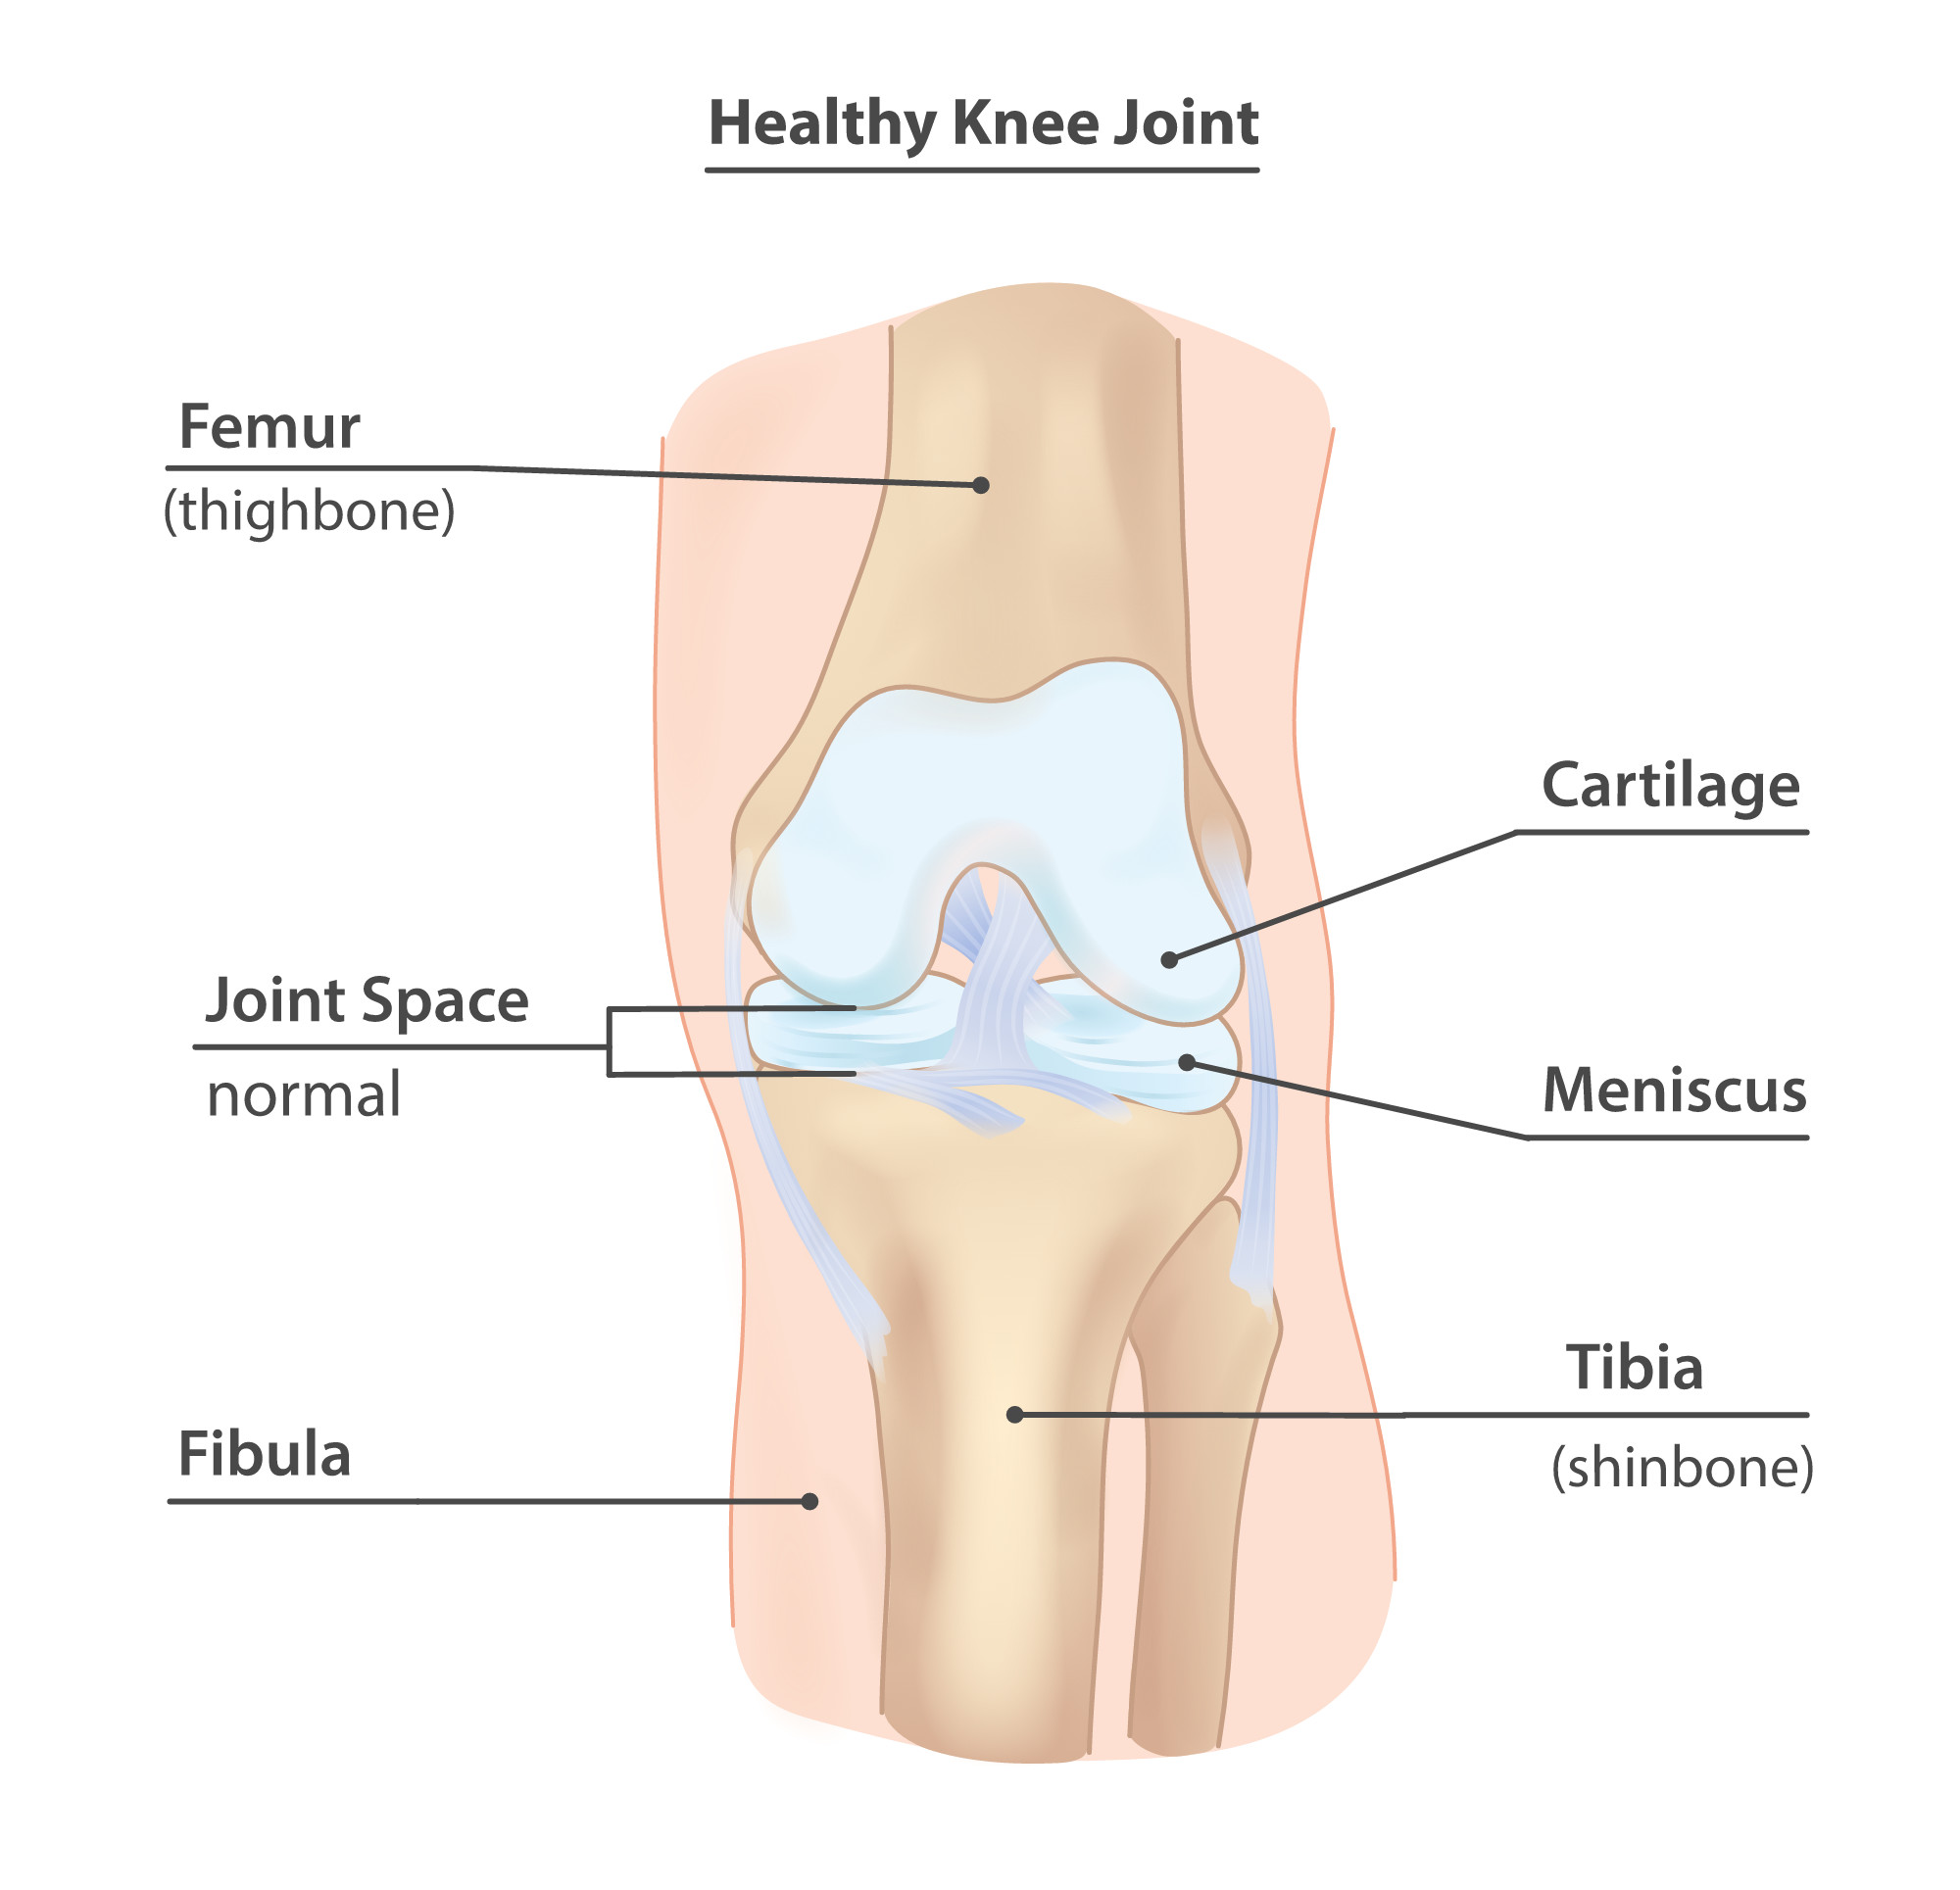

Ce se întâmplă în gonartroză?

Gonartroza reprezintă artroza genunchiului, adică uzura progresivă a cartilajului articular care acoperă suprafețele osoase ale genunchiului:

- femur

- tibie

- rotulă